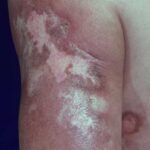

- Skin lesions are the most common manifestation of extrapulmonary disease. Cutaneous lesions favor exposed areas and enlarge over many weeks, from pimples that are minimally tender to well-circumscribed verrucous or ulcerative lesions, often with little inflammation. Verrucous lesions demonstrate raised irregular borders with crusting and purulent drainage, whereas ulcerative lesions are characterized by sharp and heaped-up borders with centrally located granulation tissue and exudate.